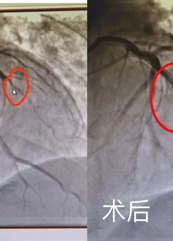

院長,畢業於江(jiāng)西(xī)醫學院,本科學曆,學士學位(wèi),曾(céng)先後在北京大學第三醫院、南昌大學第二附屬(shǔ)醫(yī)院、江西省人民醫院進修心(xīn)血管(guǎn)內科,擅長普內科、心(xīn)血管內科疾病的診治,特別在冠心病的方麵有較深造(zào)詣。

副院長,畢業於江西醫(yī)學院,本科(kē)學曆,學士學位,曾先後在南昌(chāng)大學第一附屬院、南昌大學第二附(fù)屬醫院、廣州珠江醫院(yuàn)進修(xiū)心血管內科,擅(shàn)長普內科、心(xīn)血管內科疾病診治